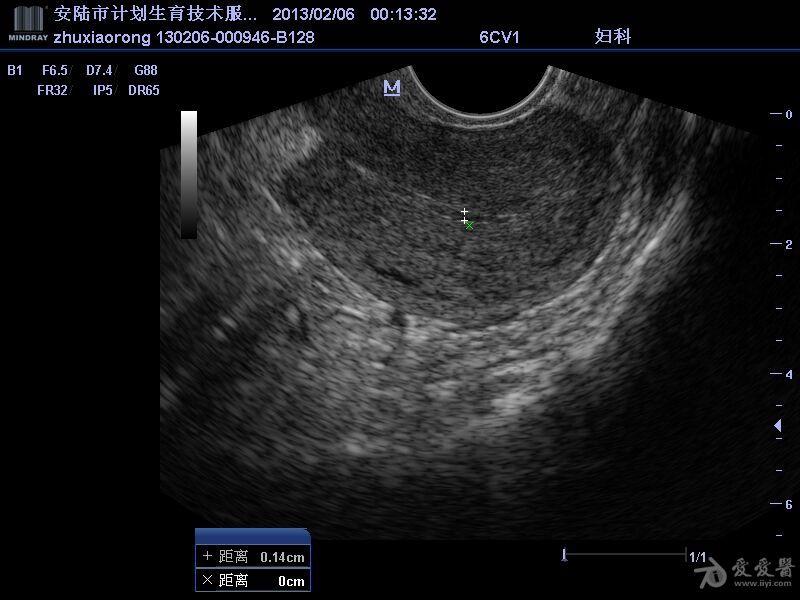

超声典型病例子宫穿孔

高手进阶:子宫穿孔的超声诊断

子宫穿孔b超图片

子宫穿孔超声图片

子宫穿孔彩超下表现

子宫穿孔超声表现图